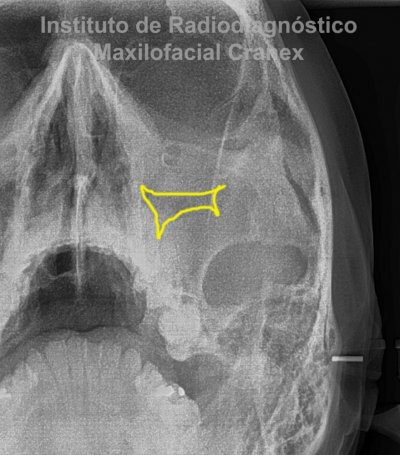

Caso Radiográfico N° 06: Sinusitis de seno maxilar en relación a comunicación buco sinusal

A la evaluación de las radiografías Panorámica, Waters, y radiografía Periapical, observamos, neumatización alveolar y opacificación parcial de seno maxilar izquierdo, lecho alveolar de correspondiente a pieza 2.6, con discontinuidad de la cortical de la pared basal de seno maxilar adyacente, y engrosamiento de la membrana antral de seno maxilar ipsilateral. Signos radiográficos compatibles con proceso inflamatorio sinusal (Sinusitis) en relación a comunicación buco sinusal.